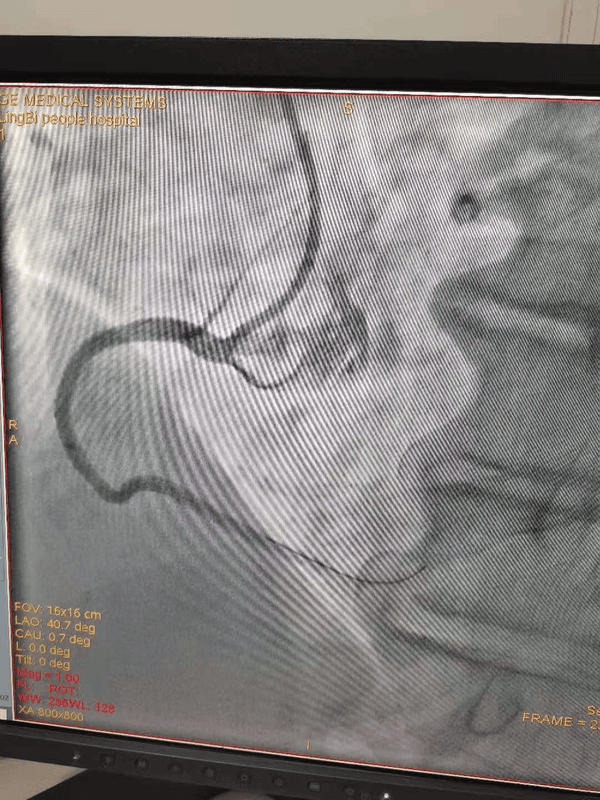

支架植入前

65岁的魏大爷因反复胸闷、胸痛入住我院心内一科,完善检查后被诊断为冠心病、心绞痛。经充分准备,予以冠脉造影+支架植入术。这是我院第一例700元左右支架手术,手术进展顺利,术中支架通过性、可塑造性、安全性均表现良好。魏大爷也幸运的成为我院第一个享受国家优惠政策的冠心病患者。